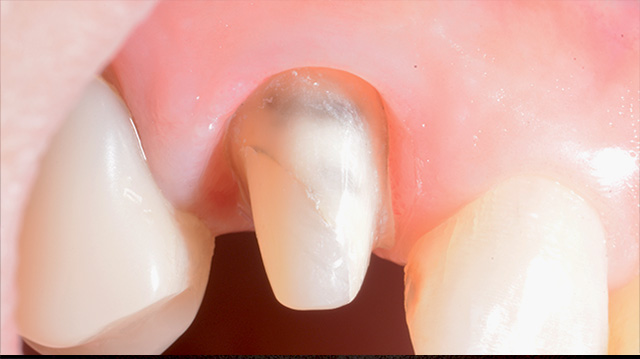

| 年代・性別 | 30代 男性 |

|---|---|

| 主訴 | 前歯の色が気になる |

| 治療期間 | 約1年 |

| 費用 |

仮歯 5,500円 × 2 ジルコニアクラウン 176,000円 × 3 インプラント 300,000円 インプラント仮歯 22,000円 サージカルガイド 70,000円 |

*キャンセルポリシーをご一読のうえご予約ください